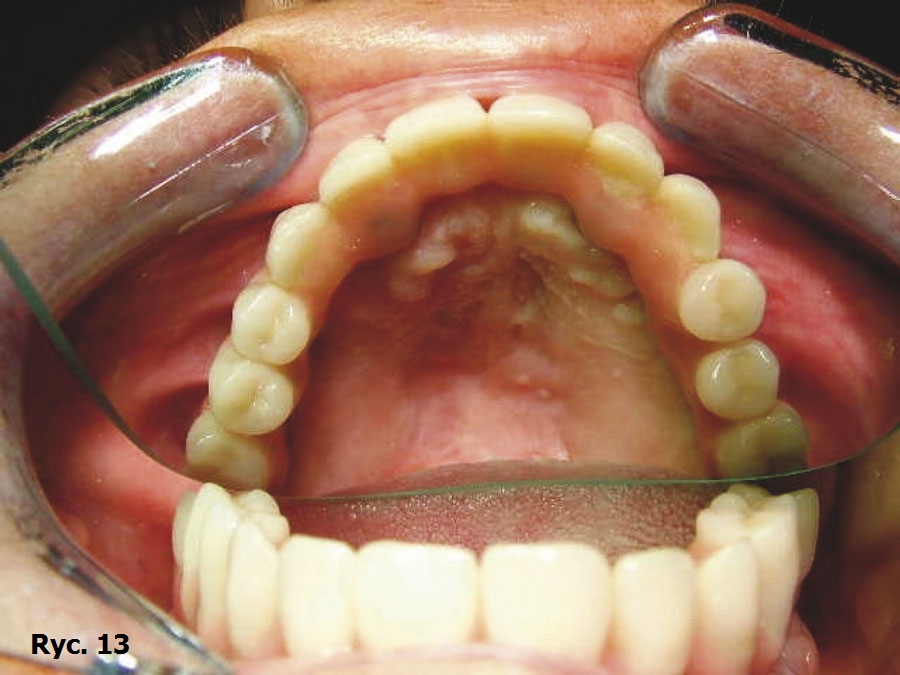

Wyniki badania TK oraz model stereolitograficzny pozwoliły na wykonanie dwóch oddzielnych siatek wszczepu podokostnowego w obrębie łuku górnego (ryc. 9), które zostały później wszczepione (ryc. 10) oraz połączone ze sobą, aby wspólnie przenosić siły żucia (ryc. 11), stanowiąc podparcie dla estetycznego uzupełnienia protetycznego stałego (ryc. 12, 13). Zabieg chirurgiczny przebiegł bez powikłań. Przysłana z Karaibów kartka pocztowa z trzema słowami „drugi miesiąc miodowy” potwierdziła, że cała wykonana przez lekarza praca zakończyła się sukcesem.